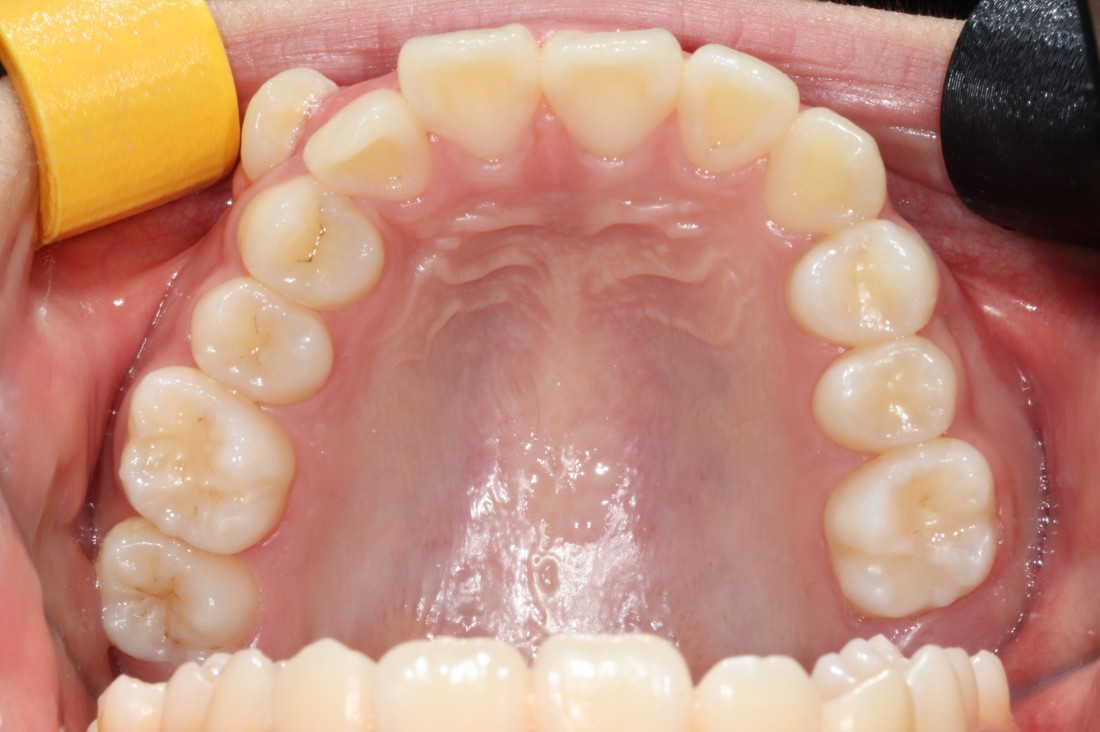

구강내과, 구강외과, 교정과

분과별 전문의 협진으로

턱 뼈 건강까지 책임지는

광주 발치교정 치과

광주 발치교정 치과에서는

구강내과, 구강외과, 교정과 전문의 협진으로

발치교정을 진행하게 됩니다.

얼굴 균형, 입술 위치, 턱뼈 상태,

잇몸 건강, 안정적인 교합까지

광주 발치교정 치과의 진료 노하우로

성공적인 발치교정을 진행합니다.